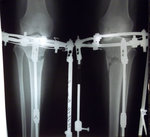

В процессе исправления деформации.

SAM_9379.JPG